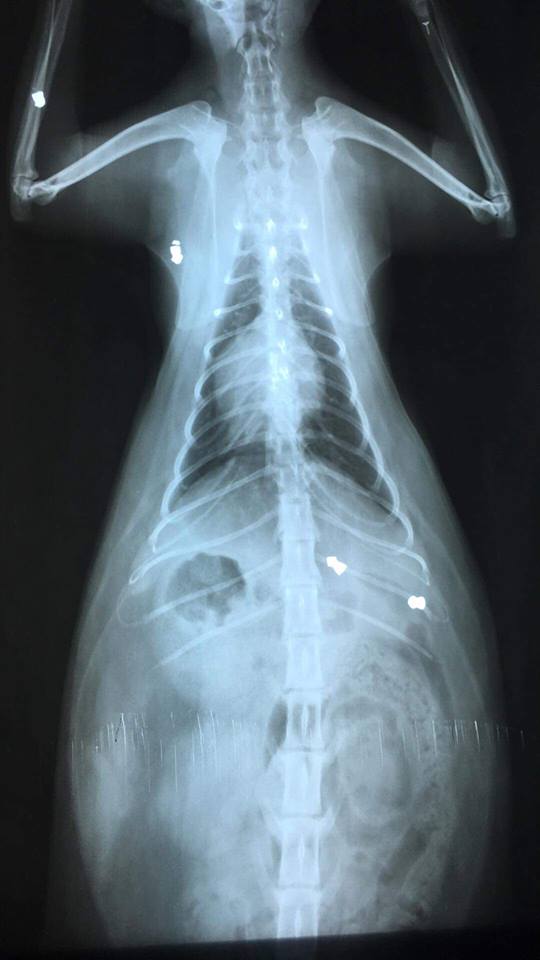

Na portalu społecznościowym na stronie należącej do jednej z przychodni weterynaryjnych na os. Ustronie pojawiła się informacja, iż nieznany sprawca z broni na śrut strzela do zwierząt. To kolejne takie zdarzenie na tym osiedlu. Tym razem kilkukrotnie został trafiony kot z ulicy Asnyka.

- fot.: FB Przychodnia Weterynaryjna lek.wet Mariusz Konarski Lubin ul.Norwida 42